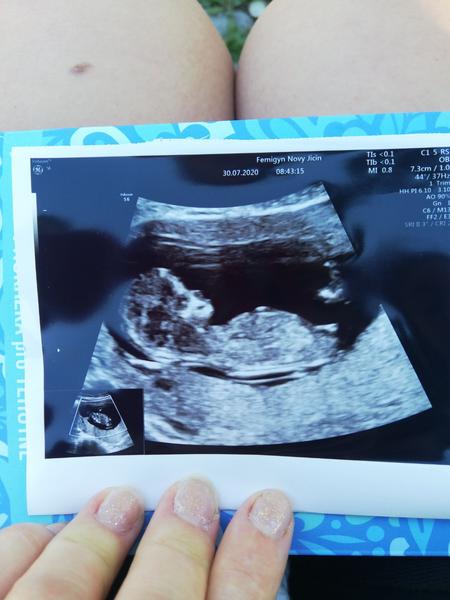

Ahoj, nepoznaly byste holky i tady?🙂